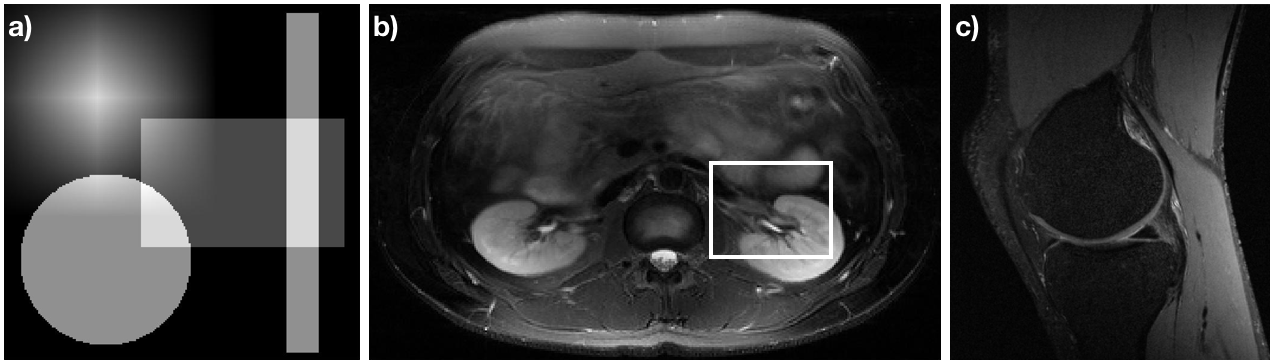

Refer to caption

Figure 1: Accurate images for data analyzed in this manuscript. (a) A numerical phantom consisting a the sum of a separable tri function, a circ function, and two separable stretched rect functions, each translated from the origin. (b) Slice 6 of the Double Vision dataset from the 2010 reconstruction challenge of the ISMRM. (c) A slice of a knee acquired from mridata.org.

The numerical phantom, shown in Fig. 1a, consists of a separable tri function, a circ function, and two separable scaled rect functions all offset from the origin and summed together. The Fourier values of this phantom are known. (The Fourier transform of a tri function is sinc2superscriptsinc2\text{sinc}^{2}, the Fourier transform of a circ is a jinc, and the Fourier transform of a rect is a sinc. When combined with the Fourier shift and scaling theorems, the Fourier values of the numerical phantom can be determined analytically.) The sample coordinates used with this phantom are radial with 360360360 spokes, 150150150 points per spoke. An image of every sixth spoke from this sample set is shown in Fig. 2a.

The image shown in Fig. 1b consists of an axial slice of an abdomen with an 888 coil acquisition from the 2010 reconstruction challenge of the International Society of Magnetic Resonance in Medicine [23]. (Slice 666 of the 121212 slice acquisition is used in this manuscript.) The method of Roemer et al. is used to combine the individual images of each coil into a single image for display [25]. The spiral trajectory created by Craig Meyer for the challenge was used, which consists of 888 spiral interleaves with 191919 revolutions per interleave. However, only every 5thsuperscript5th5^{\text{th}} sample of the readout was retained for a total of 400040004000 points per interleave. A single interleave of this set of sample coordinates is shown in Fig. 2b.

The image shown in Fig. 1c consists of a sagittal slice of a knee acquired from mridata.org. The coordinates of the sample set used for analysis is the propeller trajectory [26] with 909090 angles of acquisition (with 222 degrees difference between adjacent angular acquisitions), 999 lines per angle separated by 0.030.030.03, 200200200 points per line, and 606060 angles. Two angles for the sample set are shown in Fig. 2c.